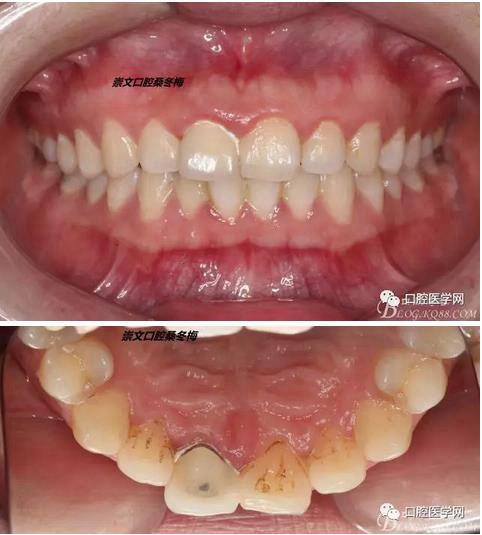

牙冠延長(zhǎng)術(shù)后6周復(fù)診牙齦齦緣形態(tài)恢復(fù)良好,齦乳頭有些欠缺,患者著急永久修復(fù)。

比色

纖維樁+樹脂核

樁道長(zhǎng)14mm

備牙

戴牙